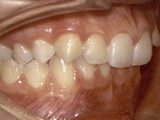

Zkřížený skus, předkus, nedostatek místa pro špičák. Léčba pomocí aparátu Hyrax a dále fixními aparáty v obou čelistech s jumping aparátem. V ústech přítomné MARA-stopy na dočasnou stabilizaci výsledku.

Před léčbou        Po léčbě

levo pac2       levo pac2